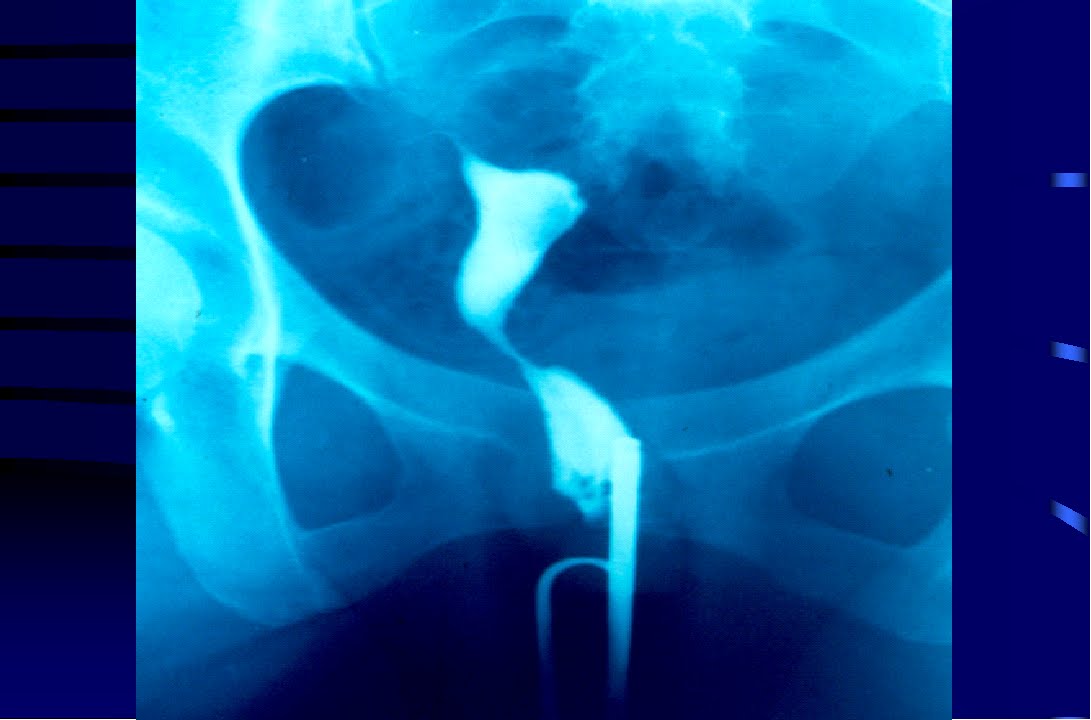

Histerossalpingografia

Histerossalpingografia é um exame radiológico (radiografias com contraste). O contraste, injetado através do colo uterino, permite verificar se as tubas uterinas estão desentupidas (pérvias) nas pacientes com dificuldade para engravidar. Miomas localizados próximos as tubas podem ser os causadores da obstrução das tubas.

-– Histerossalpingografia – Note os ossos da bacia e no centro da figura o contraste (fortemente branco) mostrando a acavidade uterina e a tuba afilada, pérvia do lado direito do corpo da paciente ( em Medicina, direito e esquerdo se referem sempre a uma pessoa que estamos olhando de frente – dizemos a mão direita da paciente, o lado direito da paciente e não a nossa referência que estamos olhando).